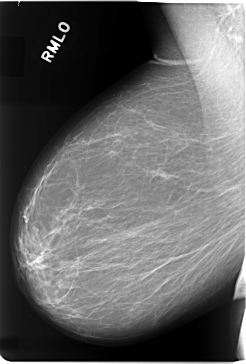

C_0082_1.RIGHT_MLO

RIGHT_CC LINES 5856 PIXELS_PER_LINE 3888 BITS_PER_PIXEL 12 RESOLUTION 50 NON_OVERLAY

RIGHT_MLO LINES 5824 PIXELS_PER_LINE 3928 BITS_PER_PIXEL 12 RESOLUTION 50 NON_OVERLAY